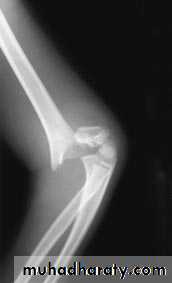

X-ray : the fracture is seen clearly in A-P ,

and lateral views . In undisplaced fracture the fat-pad sign which is triangular lucency in front of the distal humerus this will raise the suspicion of the fracture

X-ray cont. :

In A-P view we can measure the Boumans’ angle which is helpful in assessing the degree of angulation of the distal segment normally less than 80

.